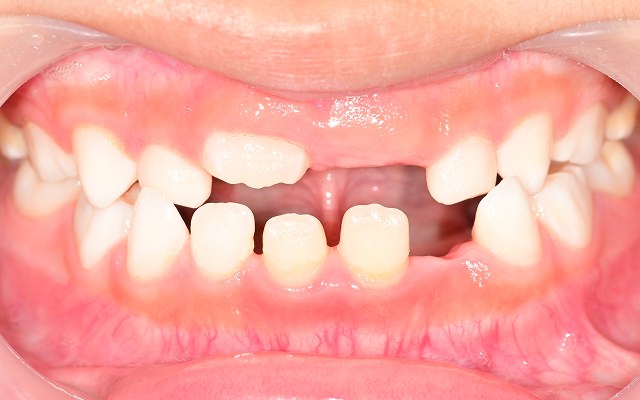

영구치가 덧니로 나거나 발치가 필요한 경우로 악화(발치교정)